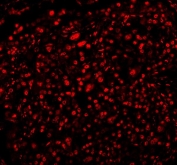

Immunofluorescent staining of FFPE human lung cancer tissue with RBFOX2 antibody (red). HIER: steam section in pH8 EDTA buffer for 20 min.